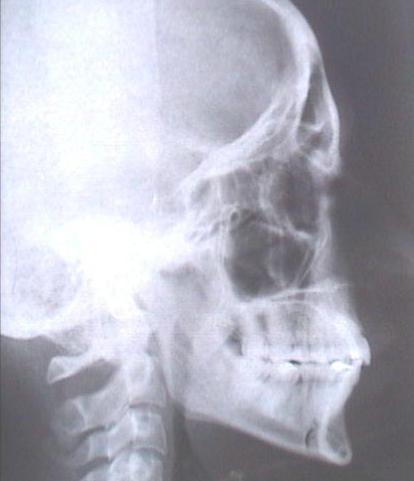

Paziente di 25 anni - Sesso femminile - Rapporti occlusali di II Classe I Divisione, retrognazia mandibolare di più di 1 DC. Tipologia dolico faciale di quasi 2 DC. Morso aperto anteriore molto esteso. Respiro orale disfunzionale con deglutizione atipica e postura della lingua fra le arcate.

Tipologia dolico faciale quasi 2 DC; II Classe I Divisione.

Importante disfunzione linguale con la lingua interposta fra le arcate, determinando il morso aperto anteriore.

L'analisi cefalometrica evidenzia un importante ipersviluppo verticale del settore dento alveolare dei primi molari superiori (16 - 26) che vengono estratti.

tele rx iniziale